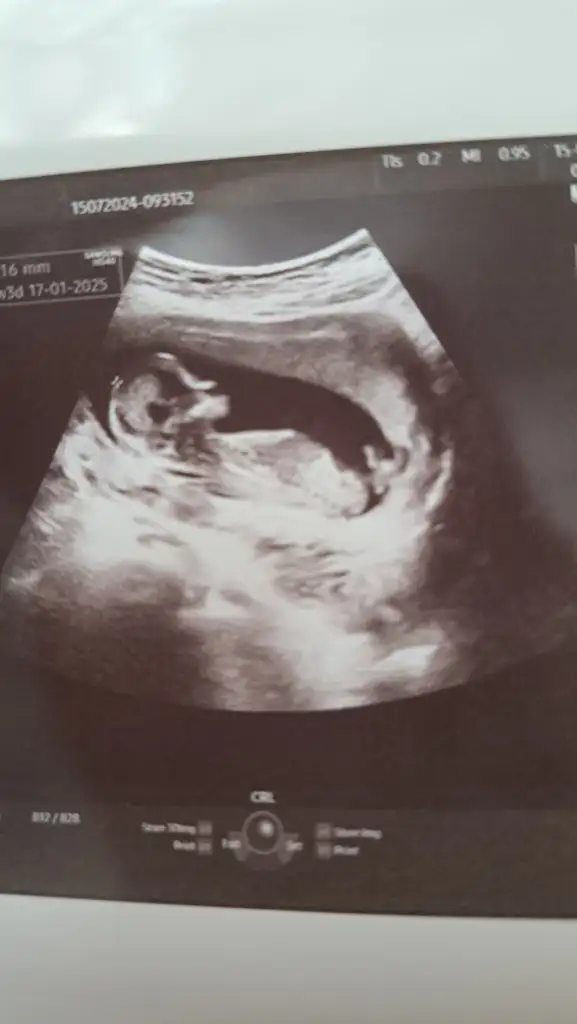

Ayy banada bakarmısınız çok merak ediyorum daha belli değil dedi doktor

İyi Akşamlar arkadaşlar bende klübe yeni katıldım 13 haftalık bebegim anlayan arkadaşlar cinsiyetine bakabilirmi doktor kız benziyor dedi ama net birşey söylemedi